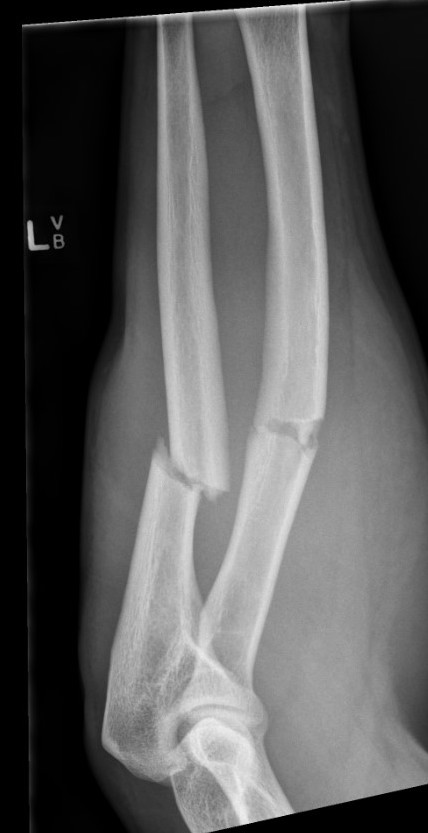

Malunion

More common with nonoperative management of pediatric forearm fractures

- loss of ROM

- failure to restore radial bow